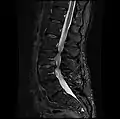

Graphic of lumbar laminectomy and two conditions it can address.

The lamina is a posterior arch of the vertebral bone lying between the spinous process (which juts out in the middle) and the more lateral pedicles and the transverse processes of each vertebra. The pair of laminae, along with the spinous process, make up the posterior wall of the bony spinal canal. Although the literal meaning of laminectomy is 'excision of the lamina', a conventional laminectomy in neurosurgery and orthopedics involves excision of the supraspinous ligament and some or all of the spinous process. Removal of these structures with an open technique requires disconnecting the many muscles of the back attached to them. A laminectomy performed as a minimal spinal surgery procedure is a tissue-preserving surgery that leaves more of the muscle intact and spares the spinal process. Another procedure, called the laminotomy, is the removal of a mid-portion of one lamina and may be done either with a conventional open technique or in a minimalistic fashion with the use of tubular retractors and endoscopes.

The reason for lamina removal is rarely, if ever, because the lamina itself is diseased; rather, it is done to break the continuity of the rigid ring of the spinal canal to allow the soft tissues within the canal to: 1) expand (decompress); 2) change the contour of the vertebral column; or 3) permit access to deeper tissue inside the spinal canal. A laminectomy is also the name of a spinal operation that conventionally includes the removal of one or both lamina, as well as other posterior supporting structures of the vertebral column, including ligaments and additional bone. The actual bone removal may be carried out with a variety of surgical tools, including drills, rongeurs and lasers.